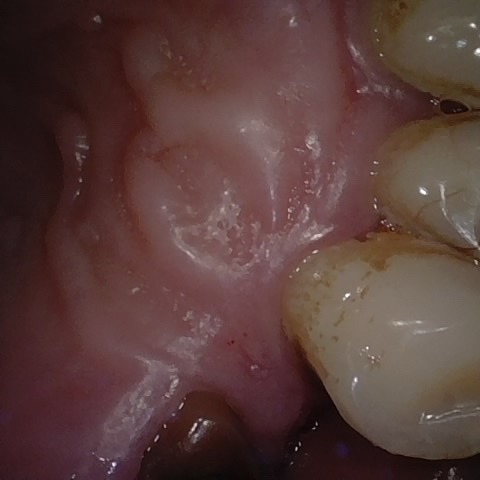

Annotated as "Good"